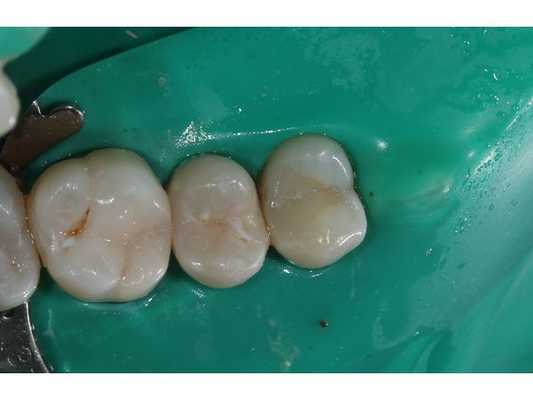

- Композитная реставрация зуба 1.6 с применением реставрационного материала — Estelite flow quick OA2, Estelite Sigma quick OA2.

- Полировка поверхности реставрации.

Эндолечение зуба 1.6 было проведено в одно посещение. Пациенту назначено прийти на контрольный осмотр через семь дней.